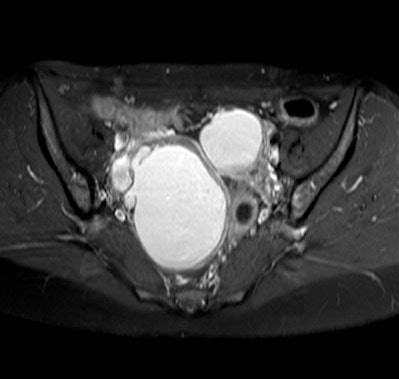

HAMBURG - MRI can be used to detect endometriomas, difficult-to-detect cells from the lining of the uterus found outside the uterine cavity, and also guide surgical intervention, according to a presentation from the 95th congress of the German Society of Radiology (DRK), 28-31 May.

Every tenth woman suffers from endometriosis, which can cause infertility and pain. Endometriomas are difficult to detect, but MRI can help, according to a study conducted by Dr. Julia Wenzel from the department of diagnostic and interventional radiology at Giessen University Hospital in Marburg, Germany.

Endometriomas may be found in places such as on the ovaries, on the bowel wall, or on the bladder. Removal by surgical intervention is the standard treatment.

"Endometriomas can take on a variety of phenotypes, including cysts and adhesions, which adds to the difficulty of identifying them in MR images," Wenzel said.

Benefits of utilizing MRI include the fact that, for cysts, the technology shows metabolites, allowing to identify the age of the cysts and to differentiate endometrial from other types of cysts.